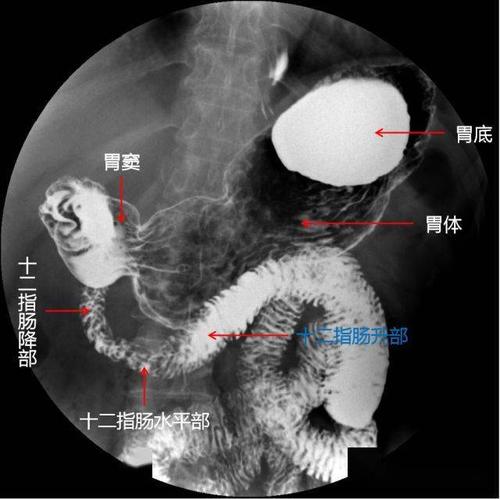

上消化道造影检查技术及常见病变的x线诊断

上消化道造影图片讲解

上消化道图解

上消化道解剖

上消化道解剖图